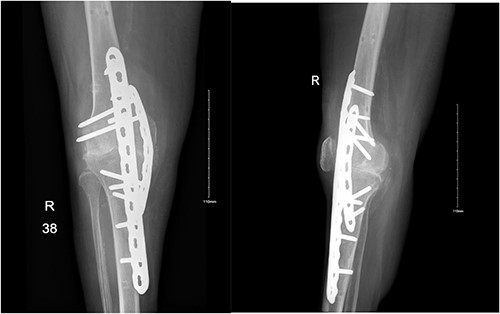

After 1-week from discharge, she presented to ED with 2 days history of right leg swelling and tenderness despite being bedbound for 3 months and denying any history of trauma. Her physical exam showed right knee swelling with absent posterior tibial artery pulse. Because of her mobility status, there was a suspicion of deep vein thrombosis (DVT); therefore, doppler ultrasound was obtained along with knee X-ray and computed tomography (CT) runoff (Fig. 1). Her doppler ultrasound showed negative results; however, knee X-ray showed posterolateral knee dislocation and CT runoff revealed evidence of septic arthritis of right knee with large intramuscular abscess extending from the popliteal fossa down to above the ankle joint adjacent to the Achilles tendon. The patient then was shifted to OR for a third I&D and a spanning external fixator application to allow for soft tissue to form enough fibrosis in order to keep the joint stable and avoid further major surgeries. At her 6-week follow-up, the external fixator was removed and the patient’s assessment showed stable knee joint and unremarkable, pre- and post-external fixator removal and X-ray.

Anteroposterior and lateral views of the knee at second presentation.